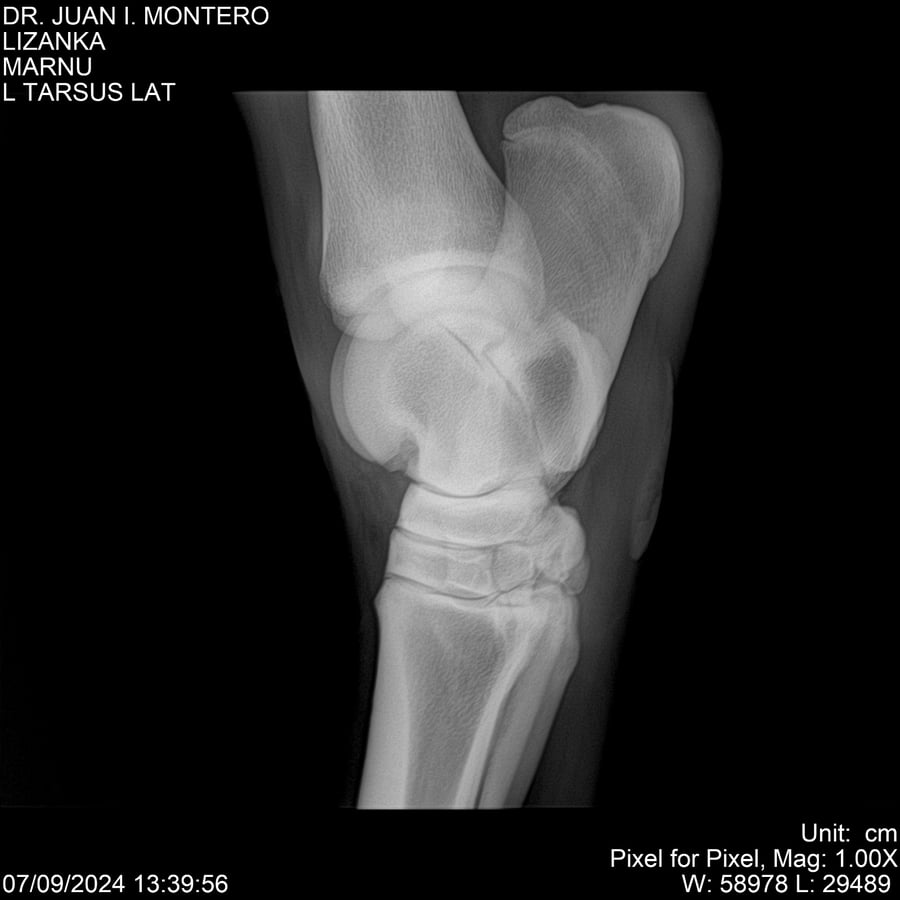

LOTE 18, LIZANKA Lote Anterior Volver al remate Lote Siguiente Ficha Contacto Montevideo - Ficha del Lote Identificador: #282512 Categoría: Yeguarizos Montevideo - 62 Visualizaciones ClicData Contacto Empresa: Abelenda N. R., Walter Hugo Nombre*: Teléfono* : E-mail* : Mensaje Enviar Registrese gratis Este contenido Exclusivo está disponible sólo para usuarios registrados Ingresar